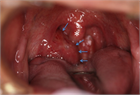

1. 扁桃肥大(アデノイド肥大を含む)は小児の睡眠時無呼吸(obstructive sleep apnea:OSA)を含む閉塞性睡眠時呼吸障害(obstructive sleep-disordered breathing:oSDB)の最も一般的な原因であり、このような小児患者に口蓋扁桃摘出術 ± アデノイド切除術は非常に有効である。一方、扁桃肥大は成長とともに軽減すること、術後出血などの術後合併症もみられることから、手術適応は慎重に評価しなければならない。成人の扁桃肥大では腫瘍性病変の可能性を念頭に置いて診断を進める必要がある。